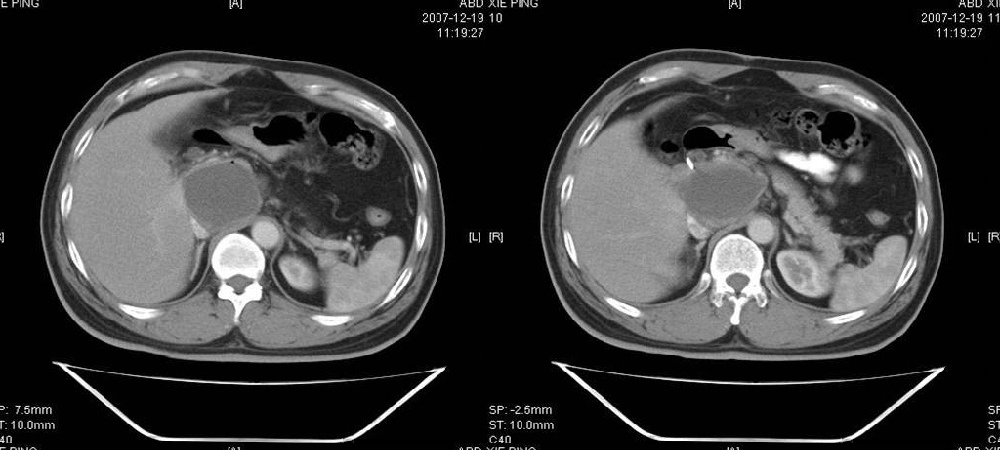

临床病史:患者,男,53岁,因反复上腹部饱胀不适2+月,在餐后或饥饿时明显,伴呃逆,无呕吐、呕血,无腹痛腹泻;2年前腹腔镜胆囊切除,否认肝炎、结核等病史。

胰腺头部低密度囊性病灶,边缘清楚,增强后囊壁略强化。考虑:胰头假性囊肿!

胰腺头部(或肝脏尾叶部)低密度囊性病灶,边缘清楚,增强后囊壁略强化。考虑:胰头假性囊肿. 或肝脏尾叶部囊肿。

考虑十二指肠憩室。从影像上看,病变位于下腔静脉前胰头后方十二指肠内侧,肝尾叶受压,说明病变来源于后腹膜;胰胆管成像胰管和胆道未见扩张,总胆管中段受压未显示,上下段正常,所以不考虑来源与于肝尾叶和总胆管的囊肿。考虑为十二指肠憩室或小网膜囊肿。

楼上高手,本例的确是一例十二指肠憩室.

考虑十二指肠憩室。从影像上看,病变位于下腔静脉前胰头后方十二指肠内侧,肝尾叶受压,说明病变来源于后腹膜;胰胆管成像胰管和胆道未见扩张,总胆管中段受压未显示,上下段正常,所以不考虑来源与于肝尾叶和总胆管的囊肿。考虑为十二指肠憩室或小网膜囊肿.分析的好。